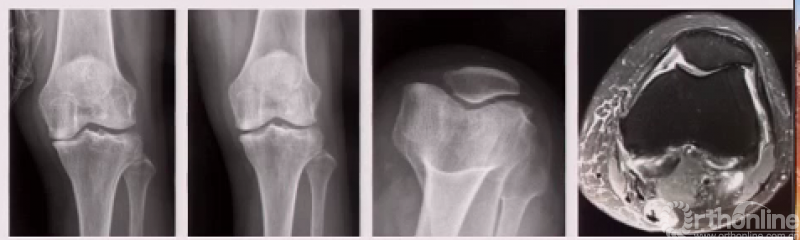

患者女性,66岁,主诉左膝关节内侧明显疼痛,保守治疗半年无效。查体显示外内侧间室磨损出现“骨对骨”,外侧间室完好。核磁显示髌股关节外侧明显退变。患者研磨试验+,无法正常下蹲。

行单髁手术,术中发现髌股关节外侧滑车软骨缺失,软骨下骨有硬化表现。

术后1年半随访,上下楼梯、下蹲等较术前均有较大改善。